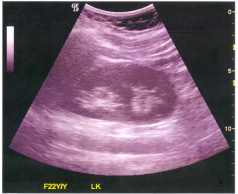

60 附圖中線狀高回音性構造最可能為下列何者?

(A) 肝鐮韌帶(falciform ligament)(B) 肝圓韌帶(round ligament)(C) 靜脈韌帶(ligamentum venosum)(D) 主肝裂(main lobar fissure)